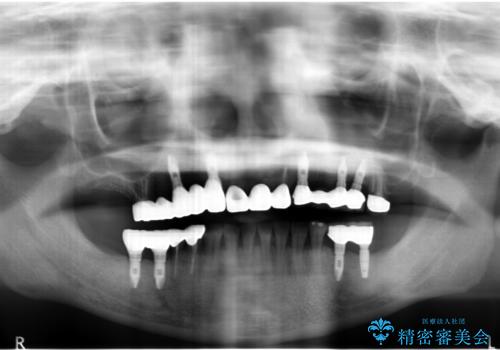

- 痛くて噛めない、これまでだましだまし治療をしてきたがこれを機にすべてきっちりと治したい、口の中の悩みを解決したいと来院されました。

抜歯や歯周病治療、欠損補綴を含め、全顎的な治療を計画・提案します。

全顎的治療について